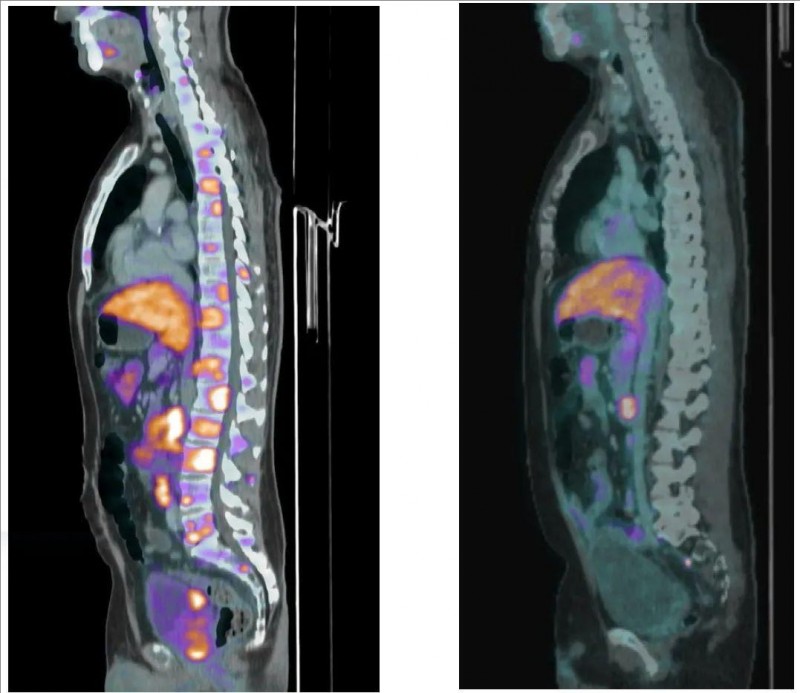

▼09号患者癌症疫苗治疗前后的PSMA PET/CT矢状面对比

▲图源“AACR”,版权归原作者所有,如无意中侵犯了知识产权,请联系我们删除

注:

①左图:治疗前(2023年5月)PSMA PET/CT矢状面显示:广泛的骨转移。

②右图:治疗后(2023年12月)PSMA PET/CT矢状面显示:所有骨转移完全消失。